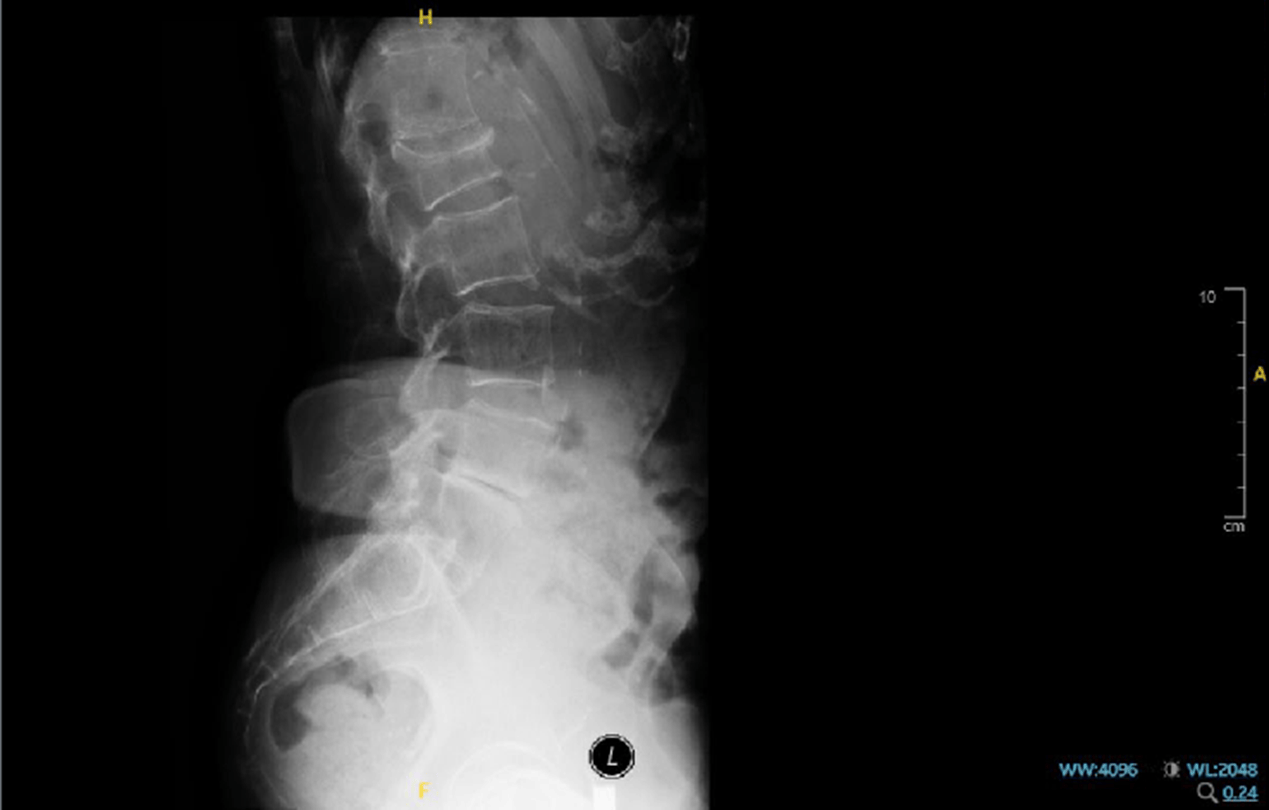

X-ray finding

- L1 fracture is observed